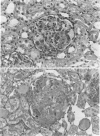

The terminal complement pathway (C5b to C9) has been demonstrated to have an important role in the mediation of glomerular immune injury in various models of experimental glomerulonephritis. In the present studies, the role of the terminal complement pathway in the accelerated autologous phase of anti-glomerular basement membrane (GBM) nephritis in the rabbit was investigated. Normocomplementemic rabbits and rabbits deficient in C6 (C6D) who are therefore unable to form the terminal complement pathway were immunized with sheep immunoglobulin G (IgG) before being injected with a subnephrotoxic dose of the gamma 2 fraction of sheep anti-rabbit GBM. C6D animals had a delay in the onset of the glomerular injury, as manifested by proteinuria. At 72 hours, controls had a greater degree of proteinuria (15.2 +/- 8.8 mg protein/mg creatinine vs. 2.6 +/- 2.1, P = 0.197), but at 120 hours there were no differences in proteinuria between C6D and control animals (11.1 +/- 3.6 mg protein/mg creatinine vs. 12.2 +/- 6.2, P = 0.89). Light microscopy demonstrated more severe glomerular injury in C6D animals with marked cellular proliferation and large areas of glomerular necrosis. Interestingly, C6D animals had significantly higher levels of sheep IgG remaining in their glomeruli at 120 hours (0.95 +/- 0.12 micrograms sheep IgG/1 x 10(4) glomeruli, N = 11, vs. 0.57 +/- 0.07, N = 11, P = 0.014) and 72 hours (1.22 +/- 0.25 micrograms, N = 3, vs. 0.60 +/- 0.15, N = 3, P = 0.104) compared with 24 hours when there was no difference (1.25 +/- 0.22 micrograms, N = 7, vs. 1.08 +/- 0.14, N = 7, P = 0.53). C6D rabbits had a greater rise in serum creatinine at 120 hours (2.3 +/- 0.5 mg/dl vs. 1.3 +/- 6.4, P = 0.132). We conclude that in C6D animals, the persistence of glomerular immune deposits is responsible for more severe renal injury and renal failure.